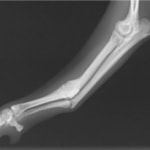

症例3:キルシュナーワイヤーのピンニングによる整復

ペルシャ猫 11ヶ月齢 雄

他院にて左大腿骨遠位の成長板骨折(salter-harrisⅠ型)が認められており、治療相談を目的として来院。当院にて、キルシュナーワイヤーを用いたピンニングにより骨折部位の整復を行いました。術後の経過は良好で、現在も経過観察中です。

術前レントゲン

術後レントゲン